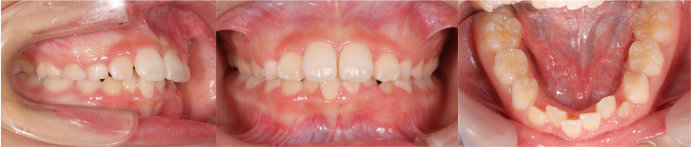

| Case9 |

| 前歯のガタガタ |

| <治療前> |

| <治療後2年後/保定後> |

| 主訴 |

上の二番目の前歯が舌側にずれて噛んでいる |

| 診断名 |

側切歯部の反対咬合を伴う叢生 |

| 年齢 |

9歳 |

| 使用装置 |

マルチブラケット装置 |

| 抜歯部位 |

永久歯の抜歯は無し |

| 治療期間 |

2年7か月 |

| 治療費概算 |

検査・診断料:5万円+税 装置・技術料:25万円+税 おおよそ1か月ごとの処置・管理料:5,000円+税 保定装置料:5万円+税 |

| リスク・副作用 |

特になし |